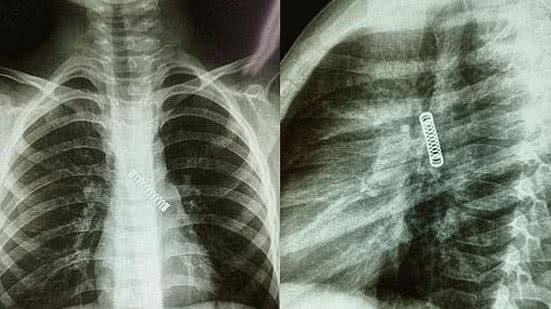

Um menino de 5 anos teve uma mola de metal removida de seu pulmão, depois do objeto ficar preso lá por três meses. O paraguaio de cinco anos sofria de uma tosse persistente desde dezembro, antes que seus pais decidissem levá-lo ao médico.

Um menino de 5 anos teve uma mola de metal removida de seu pulmão, depois do objeto ficar preso lá por três meses.

O paraguaio de cinco anos sofria de uma tosse persistente desde dezembro, antes que seus pais decidissem levá-lo ao médico.

O menino foi submetido a um raio-X e os médicos ficaram surpresos ao encontrar um objeto de metal em seu pulmão esquerdo.

De acordo com o jornal Mirror, a criança, cujo nome não foi revelado, foi tratada primeiro no Hospital Regional de Villarrica e depois foi transferida para o Instituto Nacional de Doenças Respiratórias e Ambientais para tratamento urgente. O menino agora está em condição estável depois que os médicos removeram com sucesso a mola em 8 de março.

Responsável pela cirurgia, o médico Carlos Morinigo afirmou que o procedimento foi complicado devido ao tempo que o objeto metálico ficou alojado no pulmão do menino, assim como aos danos que ele causou durante esse período.

Apesar de causar uma "provável diminuição" na capacidade do pulmão, Morinigo enfatizou que o órgão provavelmente melhorará à medida que o menino crescer com o tempo.

O médico também explicou que possivelmente a mola de metal foi engolida pela criança durante a ausência dos pais, embora não tenha sido descoberto o momento em que isso aconteceu. Além disso, ele apontou que a família não tem o costume de levar a criança ao médico para fazer exames de rotina, o que impossibilitou a identificação prévia do objeto dentro do corpo do menor.

Diante da situação, Morinigo reforça que os pais fiquem atentos com as crianças pequenas e devem sempre levá-las ao médico se desenvolverem um problema persistente.